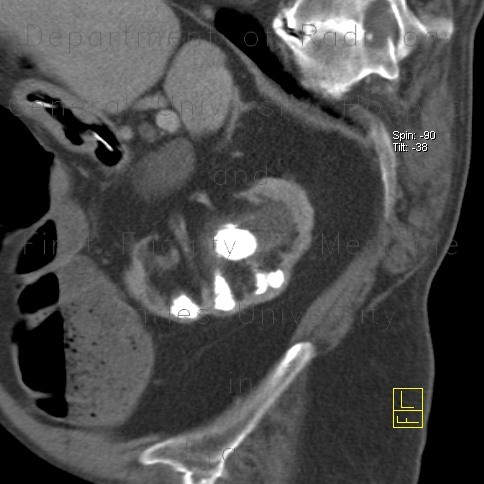

Kidney Stones

Kidney Stones Formation Kidney stones result from crystals in the urine aggregating together when the urine becomes highly concentrated. If left untreated they can cause chronic infection, destroy the kidney, and may result in death. Diagnosis ... Fetch Document